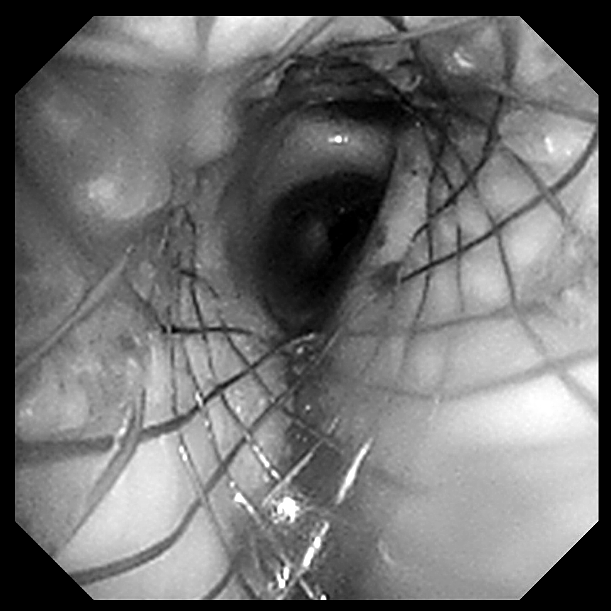

支架置入前(图 1 为 CT 冠状位,红色箭头提示肿物阻塞气道;图 2 为 CT 纵隔窗,白色箭头所指为气道肿物;图 3 为气管镜下图像,红色箭头所指为气道肿物。)

为充分保障患者安全,治疗团队决定对患者先用 ECMO 来改善氧合,之后再进行手术。重症医学科团队有条不紊地为患者进行双侧股静脉置管,连接人工肺管路,使患者血氧饱和度维持在 95% 以上。而在患者的另一边,呼吸介入团队快速插入硬质支气管镜,镜下可见患者气管下段气管已被完全堵塞。

手术团队果断进行电圈套器套切肿瘤、止血治疗,经处理后管腔明显通畅,镜下见气道肿瘤浸润范围从气管下段一直到隆突,右主气管管腔中度狭窄,呼吸介入团队在导丝引导下成功置入 Y 型覆膜支架。术后患者呼吸困难症状明显改善,欣喜的同时也感受到了自由呼吸的来之不易。